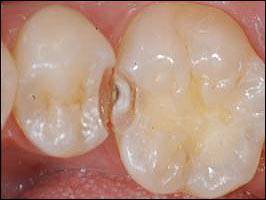

왼쪽의 사진처럼 치질이 앞뒤 좌우가 다 막혀 있지 못하고 한쪽 면이 열려 있는 경우에 아말감은 제 기능을 못할 때가 잦다.

한쪽 면이 열린 충치(이하 2급 와동)의 경우 아말감으로 수복할 경우 치아끼리 맞닿는 부분을 정확하게 형성하기 어렵기 때문에 끝 부분이 허물어지거나 음식물이 끼는 경우가 많다. 끼인 음식물을 방치할 경우 해당 부위의 이와 잇몸은 빠른 속도로 파괴된다.